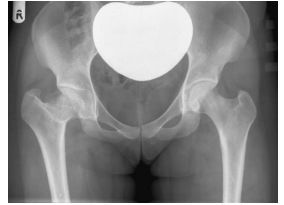

A proteção gonadal em radiografias de quadril e fêmur é um item

muito importante da proteção radiológica.

Baseado na imagem abaixo, assinale a afirmativa correta.